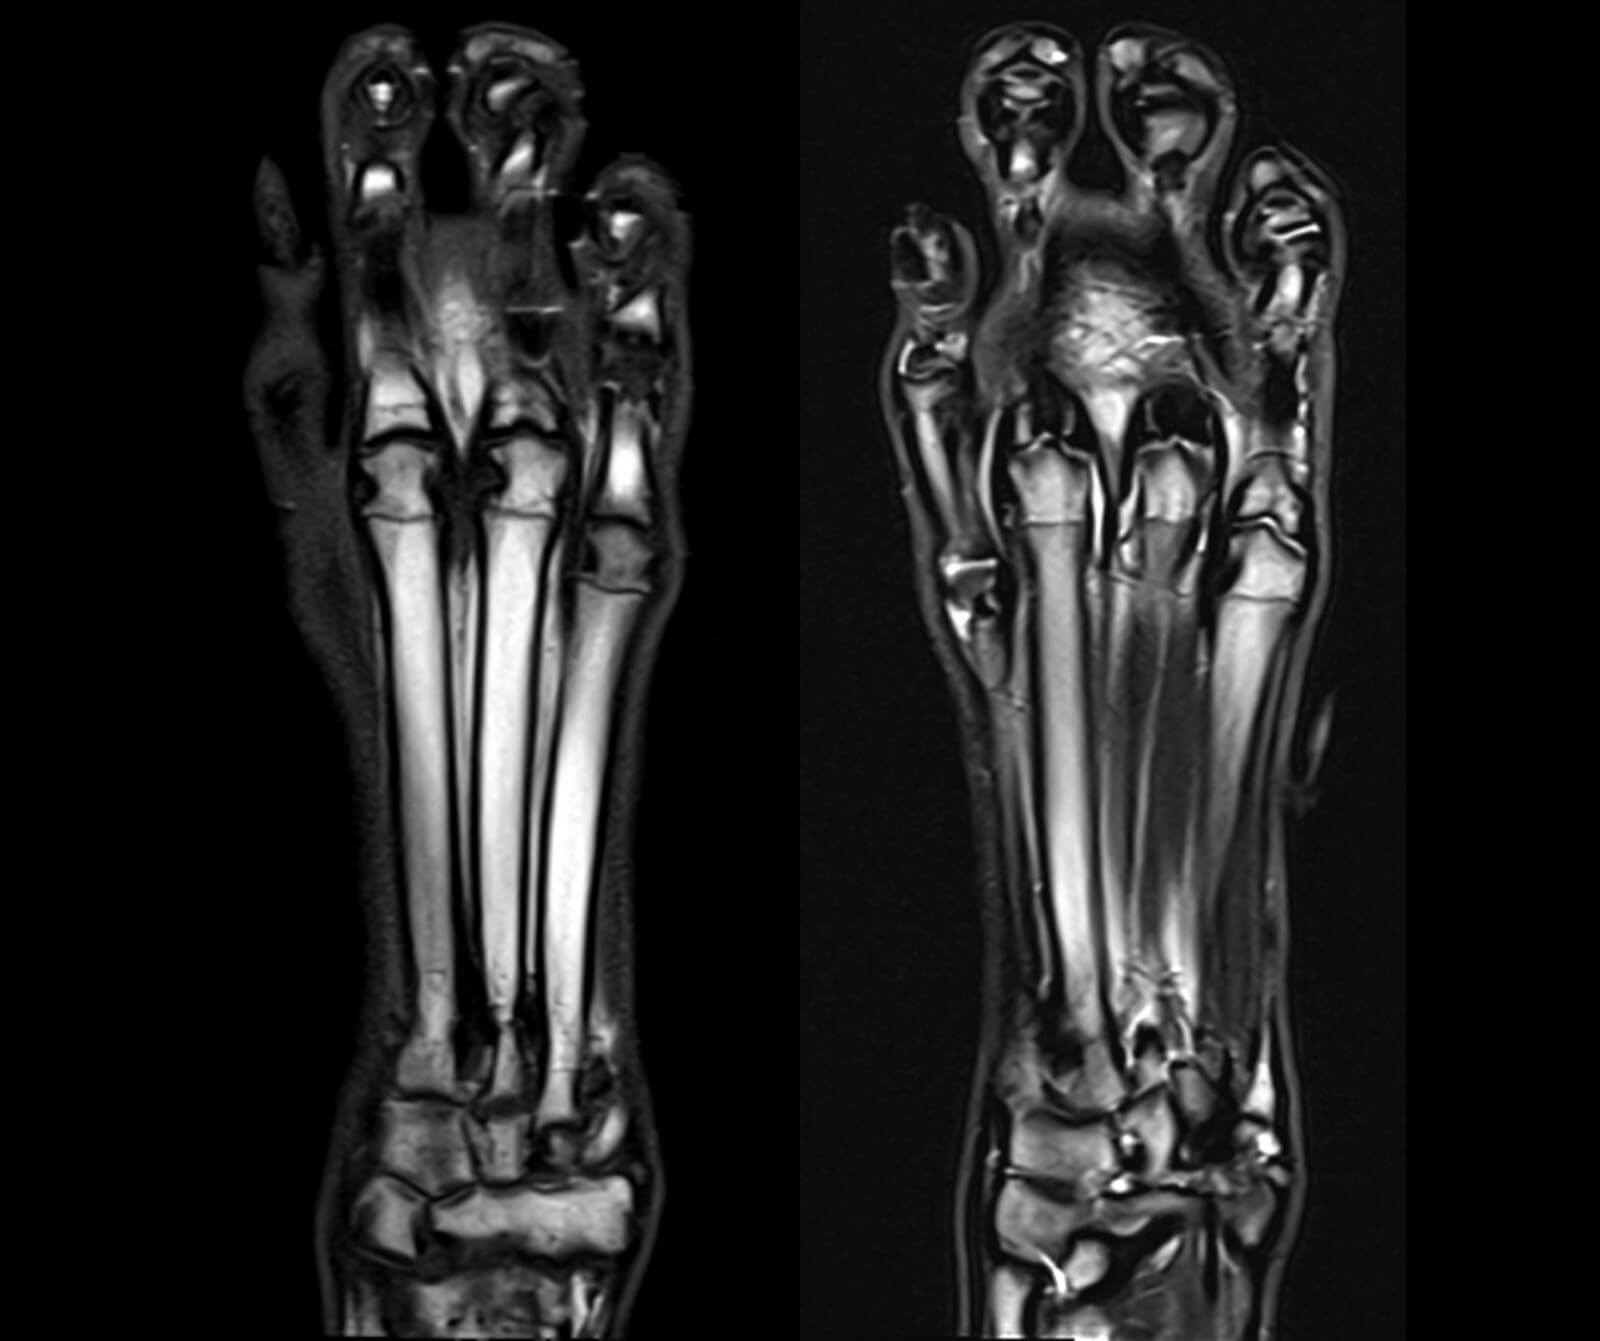

Veteriner hekimliğinde MR; beyin, omurilik, sinir sistemi, kas-iskelet sistemi ve iç organ hastalıklarının değerlendirilmesinde kritik rol oynar. Kemik yapılar dâhil olmak üzere vücudun tüm bölgeleri MR ile ayrıntılı şekilde incelenebilir.

• Kas, bağ, tendon ve eklemler gibi yumuşak dokular